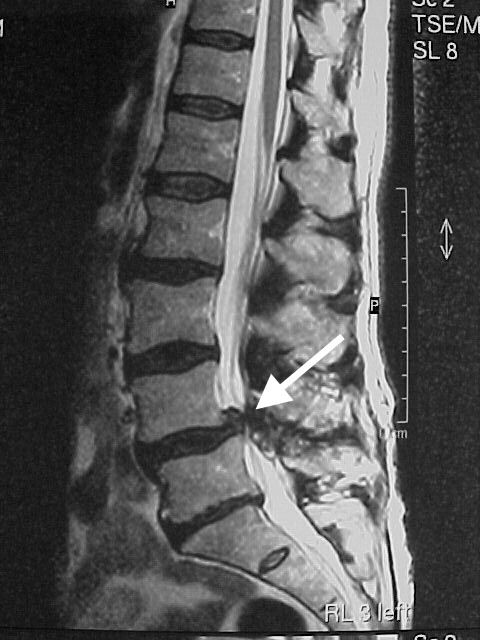

Грыжа диска на МРТ позвоночника. Стоит ли паниковать?

• При разрыве фиброзного кольца мягкая внутренняя часть диска (пульпозное ядро) выходит за пределы диска - это грыжа.

Когда размер имеет значение.

Грыжи межпозвонковых дисков в поясничном отделе, размер которых не превышает 5 мм, считаются незначительными с клинической точки зрения и как правило не вызывают болевых ощущений.

Однако и грыжи, размер которых превышает 5 мм, не всегда становятся источником боли!

Всё определяется их локализацией относительно нервных окончаний и спинного мозга, а также другими сопутствующими патологиями в позвоночнике.